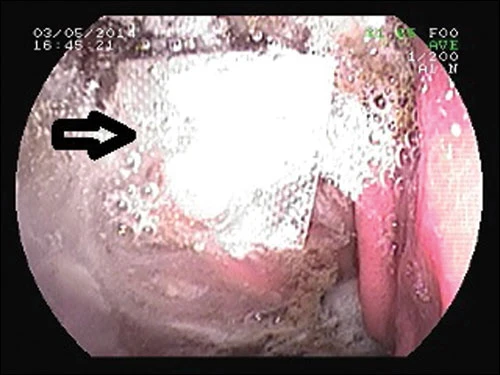

Viên thuốc trong vỉ nằm lẫn với thức ăn trong dạ dày